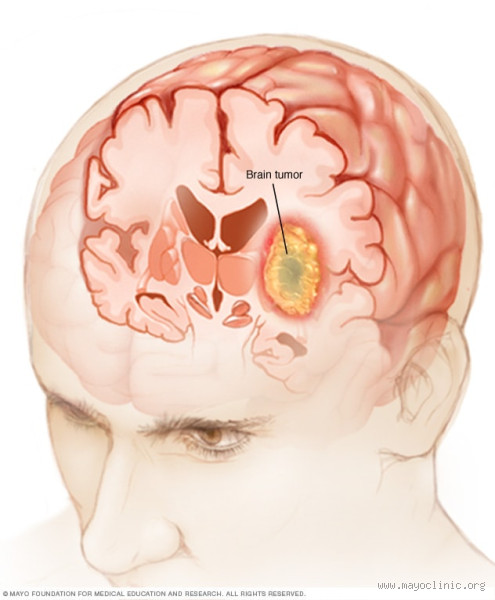

من أول الأشياء التي يمكن أن تتبادر إلى ذهنك عند سماع كلمة "ورم دماغي خبيث" هي الخوف والقلق. وربما تتساءل عن ماهية هذا الورم وأسبابه. في الواقع، الورم الدماغي الخبيث هو نوع من الأورام التي تنشأ في الدماغ، وهي تتميز بالنمو السريع وغير المنضبط للخلايا السرطانية. هذه الأورام يمكن أن تكون خطيرة للغاية لأنها تؤثر على وظائف الدماغ الحيوية.

بصراحة، الإجابة ليست بسيطة كما قد تبدو. هناك علاج، لكنه يعتمد على عدة عوامل، مثل نوع الورم، مكانه في الدماغ، ومدى انتشاره. العلاج يمكن أن يشمل الجراحة، العلاج الإشعاعي، والعلاج الكيميائي. لكن، للأسف، لا يوجد علاج واحد سحري لكل الحالات. قد يختلف العلاج بشكل كبير من مريض لآخر.

عندما يكون الورم في مكان يسهل الوصول إليه، يمكن أن تكون الجراحة هي الخيار الأول. الهدف هو إزالة أكبر قدر ممكن من الورم دون التسبب في ضرر لبقية الدماغ. في بعض الحالات، قد لا يكون من الممكن إزالة الورم بالكامل، ولكن حتى إزالة جزء منه يمكن أن يساعد في تخفيف الأعراض.

إذا كانت الجراحة غير ممكنة، أو إذا كان الورم قد عاد بعد الجراحة، يتم اللجوء إلى العلاج الإشعاعي. هذا العلاج يستخدم أشعة قوية لقتل الخلايا السرطانية أو إيقاف نموها. في بعض الحالات، قد يُستخدم العلاج الكيميائي أيضًا، الذي يستهدف الخلايا السرطانية في جميع أنحاء الجسم.